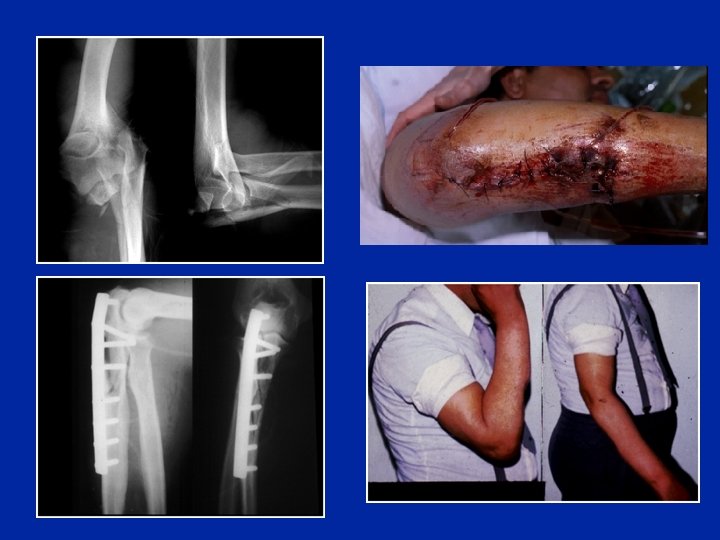

Fracture de Monteggia Fracture du cubitus + Luxation de la tête du radius

Traitement de la fracture de Monteggia - Réduction - Ostéosynthèse “anatomique“du cubitus - Le radius est alors stable

Fracture de Monteggia comminutive ouverte